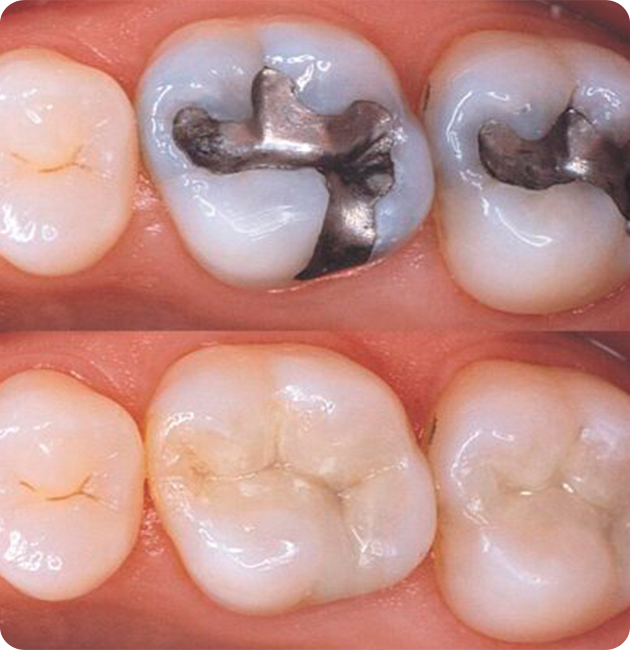

Composite Resin Fillings

• Material: Tooth-colored blend of plastic and glass.

• Pros: Blends naturally with your teeth; ideal for visible areas.

• Cons: Less durable than metal; may need replacement in 5–10 years.